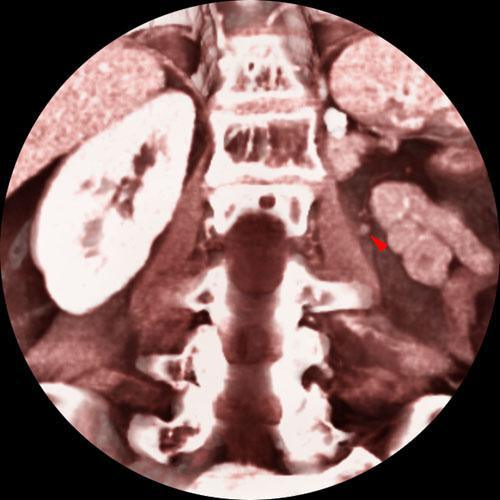

Nefrectomía parcial. Tumorectomia